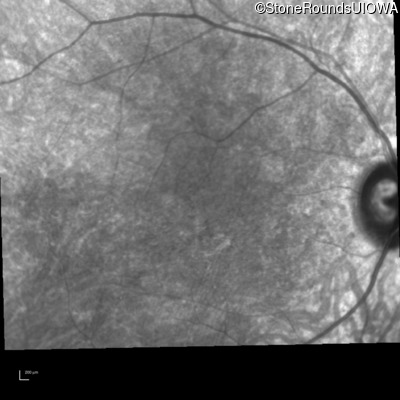

Infrared Fundus Photograph - Right - 20/200 +2

Exemplar

Infrared Fundus Photograph - Left - 20/200 +2